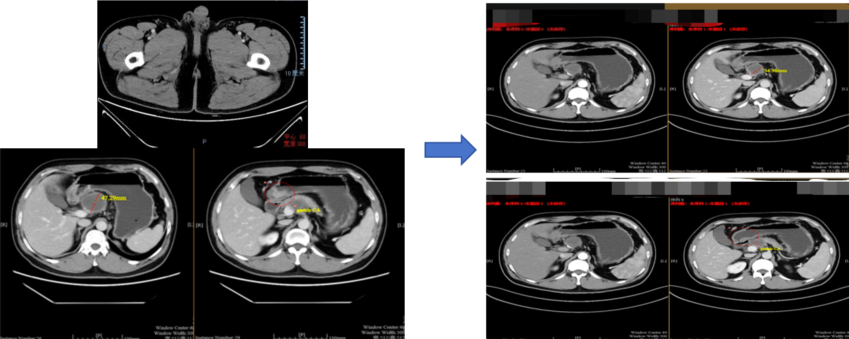

治疗2周期后(2021年10月8日):复查CT示靶病灶淋巴结缩小至35mm,缩小26%,疗效评估为疾病稳定(SD)。

c9b2e20a-a23e-4d1f-b6ce-211177146e98.png

治疗前对比治疗2周期后疗效评估

治疗3周期后(2021年11月3日):复查CT示靶病灶淋巴结缩小至29.9mm,缩小37%,疗效评估为部分缓解(PR)。

e51f106d-3b8c-421b-a587-6b609a7a1db6.png

治疗前对比治疗3周期后疗效评估